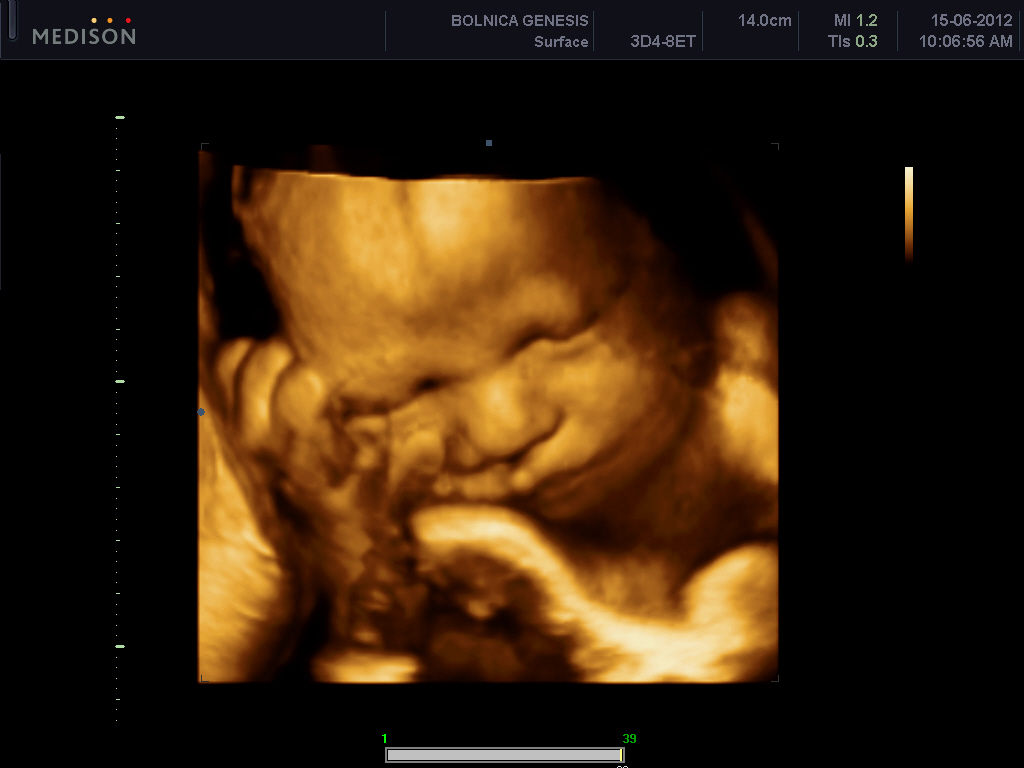

Ultrazvuk – udarac na zdravlje još nerođene dece

Ultrazvuk može štetno uticati na razvoj mozga fetusa, pa se trudnice stoga ne bi trebale izlagati čestim i nepotrebnim ultrazvučnim pregledima. Reč je o zaključku tima naučnika sa univerz